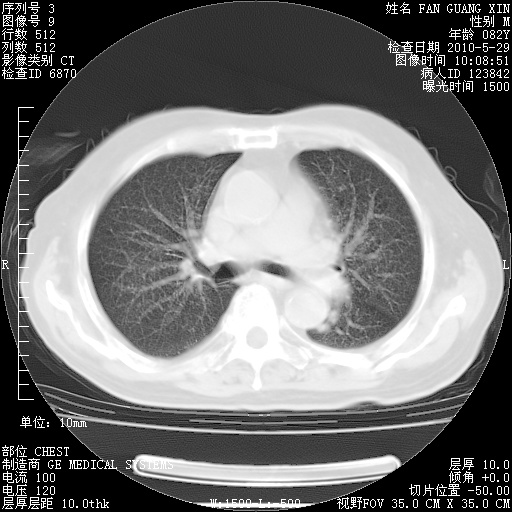

再治疗10天后的肺部CT